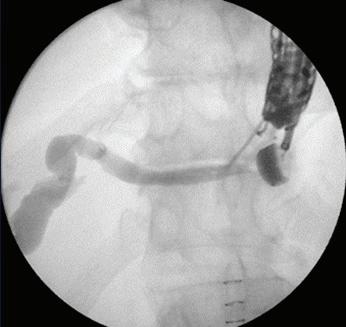

Ехоендоскопският билиарен дренаж обединява в себе си няколко техники и две въз -

можности за достъп - трансхепатален и екстрахепатален. В зависимост от наличието

или не на дилатация на интрахепаталните жлъчни пътища може да се извърши хепатикогастростомия, холедоходуоденостомия или антеградно стентиране.

Възможна е и „рандеву“ процедура, при

която с интра- или екстрахепатален достъп се въвежда